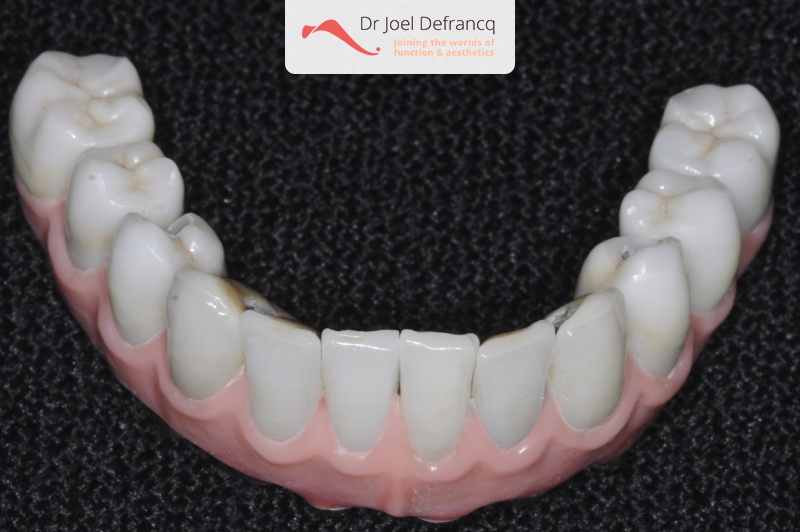

Behandeling tandheelkundige implantaten

- Vaste tanden op implantaten (bovenkaak)

- Vaste tanden op implantaten (onderkaak)